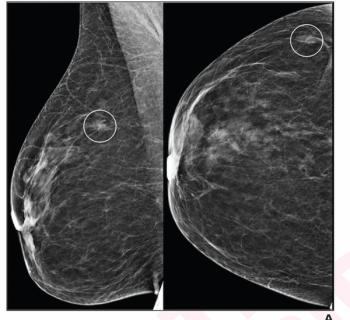

Digital breast tomosynthesis (DBT) and synthesized mammography offered a true-positive recall rate of 8.4 per 1,000 women screened vs. 6.2 for digital mammography alone, according to a study involving over 99,000 women.

While the AI software offered nearly equivalent negative predictive value (NPV) to radiologist interpretation of digital mammograms and digital breast tomosynthesis (DBT) images, researchers noted that AI had significantly higher recall rates and false-positive results in patients with intermediate risk.